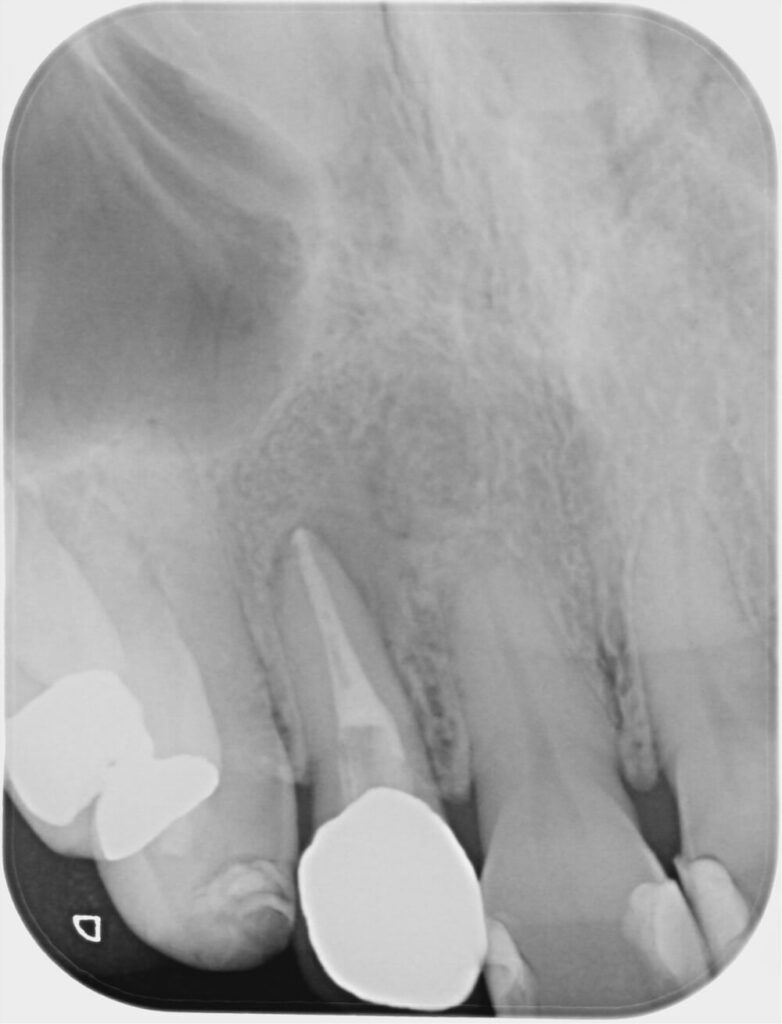

レントゲン(デンタルX線)では 根の先に2cm以上の大きな骨吸収 が確認されました。

■術前→ 1年6か月後の変化

初診時(左) 1年6か月後(右)